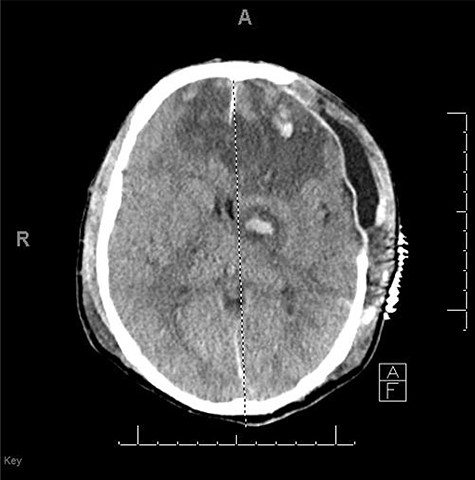

A 59-year-old male was found in the street with a head laceration. He was brought to the trauma bay as a pedestrian struck trauma patient with a prehospital GCS of 3. On arrival, his GCS was 11 (E3, V2, M6). An expanding neck hematoma was seen on exam. CT scan revealed scattered bilateral frontal contusions with hemorrhage in right basal ganglia, small bilateral acute SDH without significant mass effect, minimally displaced right temporal/occipital skull fracture and right-sided rib fractures 1–7 (flail chest) with hemopneumothorax (Fig. 1).